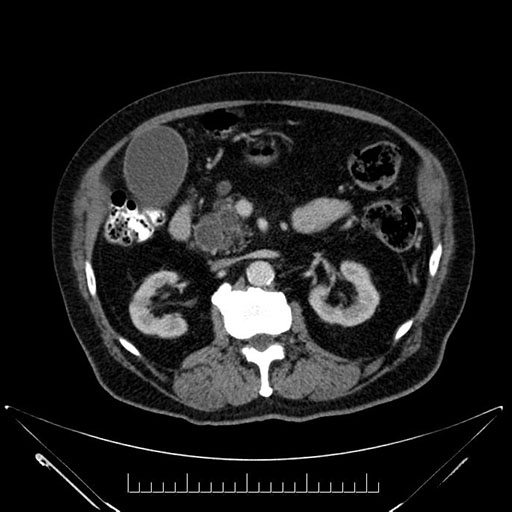

Axial - 3 months prior